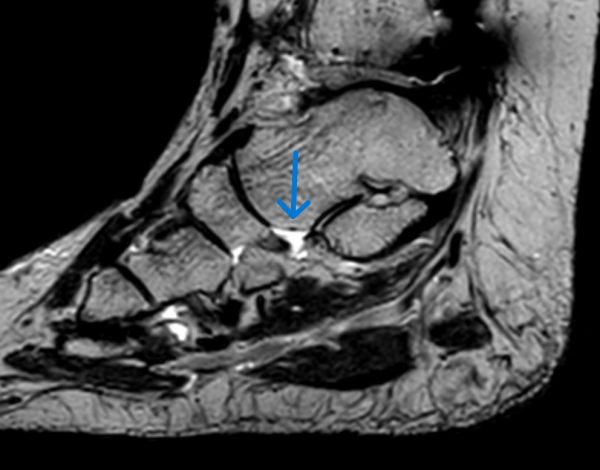

MRT-Untersuchung

Die Magnetresonanztomographie (MRT) ermöglicht eine detaillierte Darstellung der Tibialis-posterior-Sehne sowie angrenzender Weichteilstrukturen. Hierdurch lassen sich degenerative Veränderungen, Entzündungen oder Teilrisse der Sehne zuverlässig erkennen.

Die MRT spielt eine zentrale Rolle bei der Stadieneinteilung der Erkrankung sowie bei der Planung konservativer und operativer Therapien.

Vorsicht: Das für den Arzt bei der Untersuchung offensichtliche Tibialis-posterior-Syndrom muss sich nicht im MRT als darstellbare strukturelle Veränderung zeigen. Dafür gibt es nach unserer Erfahrung drei wesentliche Gründe:

- Ganz zu Beginn eines Tibialis-posterior-Syndroms sind noch keine nachweisbaren strukturellen Veränderungen aufgetreten

- Um die Tibialis-posterior-Sehne im MRT gut darstellen zu können, ist eine spezielle Technik und Einstellung am MRT nötig

- Die Ortsauflösung älterer MRT Geräte ist oft nicht sehr gut, so dass kleine Veränderungen der Tibialis-Posterior-Sehne mit solchen Geräten nicht nachgewiesen werden können